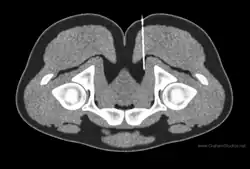

Illustration of a CT image-guided injection of the pudendal nerve at the pudendal canal

Diagnostic nerve blocks can confirm the clinical diagnosis for chronic pain as well as identify the entrapment site.[5] A diagnostic block is like an inverted palpation in the sense that palpation will cause a sensory nerve to send a signal (action potential) and a block will prevent a sensory nerve from sending a signal. By blocking nerve signals, the pain-contributing nerves can be identified or ruled out. Nerves are predisposed to entrapment in certain anatomical regions such as in an osteofibrous tunnels, through a muscle, adjacent to fibrous tissue.[6] Consequently, knowledge of these anatomical regions as well as peripheral nerve anatomy is an essential component to planning successful diagnostic blocks.[5] Ultrasound is a common form of image-guidance to place the needle properly, but it faces limitations visualizing small and deep nerves.[7] CT- or MRI- guidance are better positioned to access deep nerves as well as identify the anatomic level of the needle.[7]